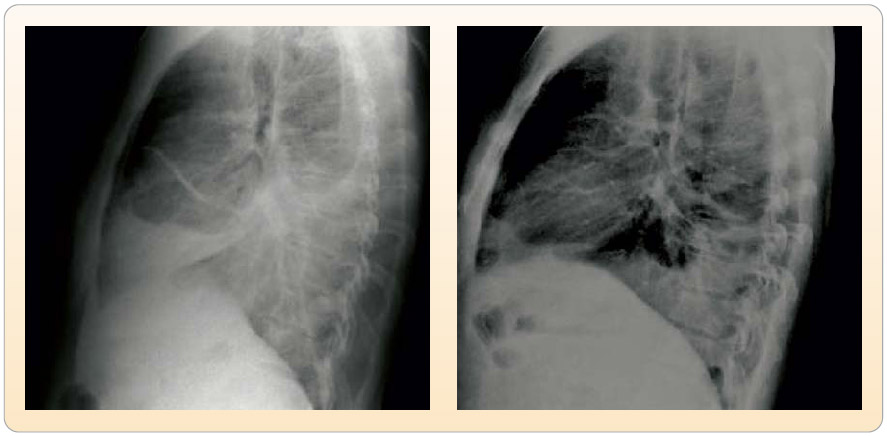

Obr. 4  Zadopřední skiagramy před zahájením terapie erlotinibem u druhé pacientky a po 2 měsících léčby – okrouhlá infiltrace vlevo centrálně. Druhá žena, u které byl zjištěn adenokarcinom dolního laloku levé plíce ve věku 33 let, byla přijata na naše pracoviště již po léčbě první i druhou linií chemoterapie. Původní nádor adenokarcinom byl histologicky verifikován z odebrané krční uzliny v květnu roku 2006, v době diagnózy již bylo onemocnění pokročilé s metastatickým postižením jater, některých obratlů a krčních uzlin, současně byly postiženy mediastinální uzliny, primární plicní nádor postihoval šestý segment levé plíce (T3N2M1). Tato pacientka podstoupila paliativní analgetické ozáření na oblast bederní a sakrální páteře v dávce 30 Gy v období 5–6/2006 na radiačním Obr. 5  Boční skiagramy druhé pacientky před zahájením terapie erlotinibem a po 2 měsících léčby – okrouhlá infiltrace v segmentu 6. oddělení Masarykova onkologického ústavu (MOÚ), v této době probíhala na MOÚ i systémová chemoterapie první linie – celkem tři cykly cisplatiny s gemcitabinem bez léčebné odpovědi, nádorové onemocnění progredovalo v plicích i v játrech. Na stejném pracovišti následovalo podávání chemoterapie druhé linie – celkem 7 aplikací docetaxelu, tato léčba byla ukončena v lednu roku 2007 s efektem další progrese. Po celou dobu užívala nemocná v rámci komplexní paliativní léčby kostních metastáz bisfosfonáty. Vzhledem k progresi po obou liniích chemoterapie byla pacientka při dobrém PS 1 odeslána ke zvážení další léčby na naše pracoviště. Vzhledem k věku nemocné, dobrému biologickému stavu a histologickému typu byla zahájena ve třetí linii terapie erlotinibem bez větších nežádoucích účinků (aplikace 2–9/2007). Hned po prvním měsíci užívání byla patrná regrese primárního nádorového uzlu v plicích (obr. 45) i regrese metastatického postižení jater. Po téměř 6 měsících léčby erlotinibem byla při kontrole zjištěna progrese zejména jaterních metastáz, proto byla tato léčba ukončena. Pacientka zemřela za příznaků další progrese nádorového onemocnění dne 6. 4. 2008, tedy téměř za 7 měsíců od ukončení terapie erlotinibem, celkově tato pacientka přežívala od doby stanovení diagnózy při třech liniích léčby 23 měsíců. Od počátku se jednalo o IV. klinické stadium nemoci s metastatickým postižením jater, skeletu a krčních uzlin.